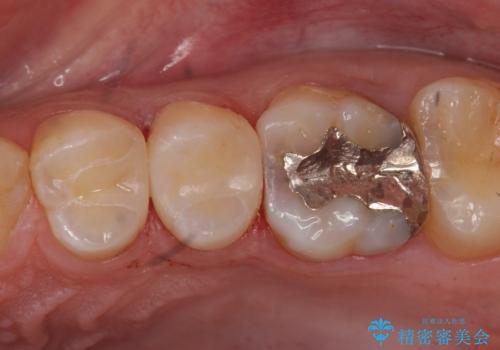

コンタクトカリエスの治療

- 虫歯の検査のために来院された患者さまです。

レントゲンで診査したら、歯と歯の間に虫歯(コンタクトカリエス)が見られたので

e-maxインレーで治療を行いました。

コンタクトカリエスは歯ブラシでは磨くことはできないため、虫歯になりやすい箇所の一つです。

毎日のフロスを行うことでコンタクトカリエスを防ぐ事ができます。